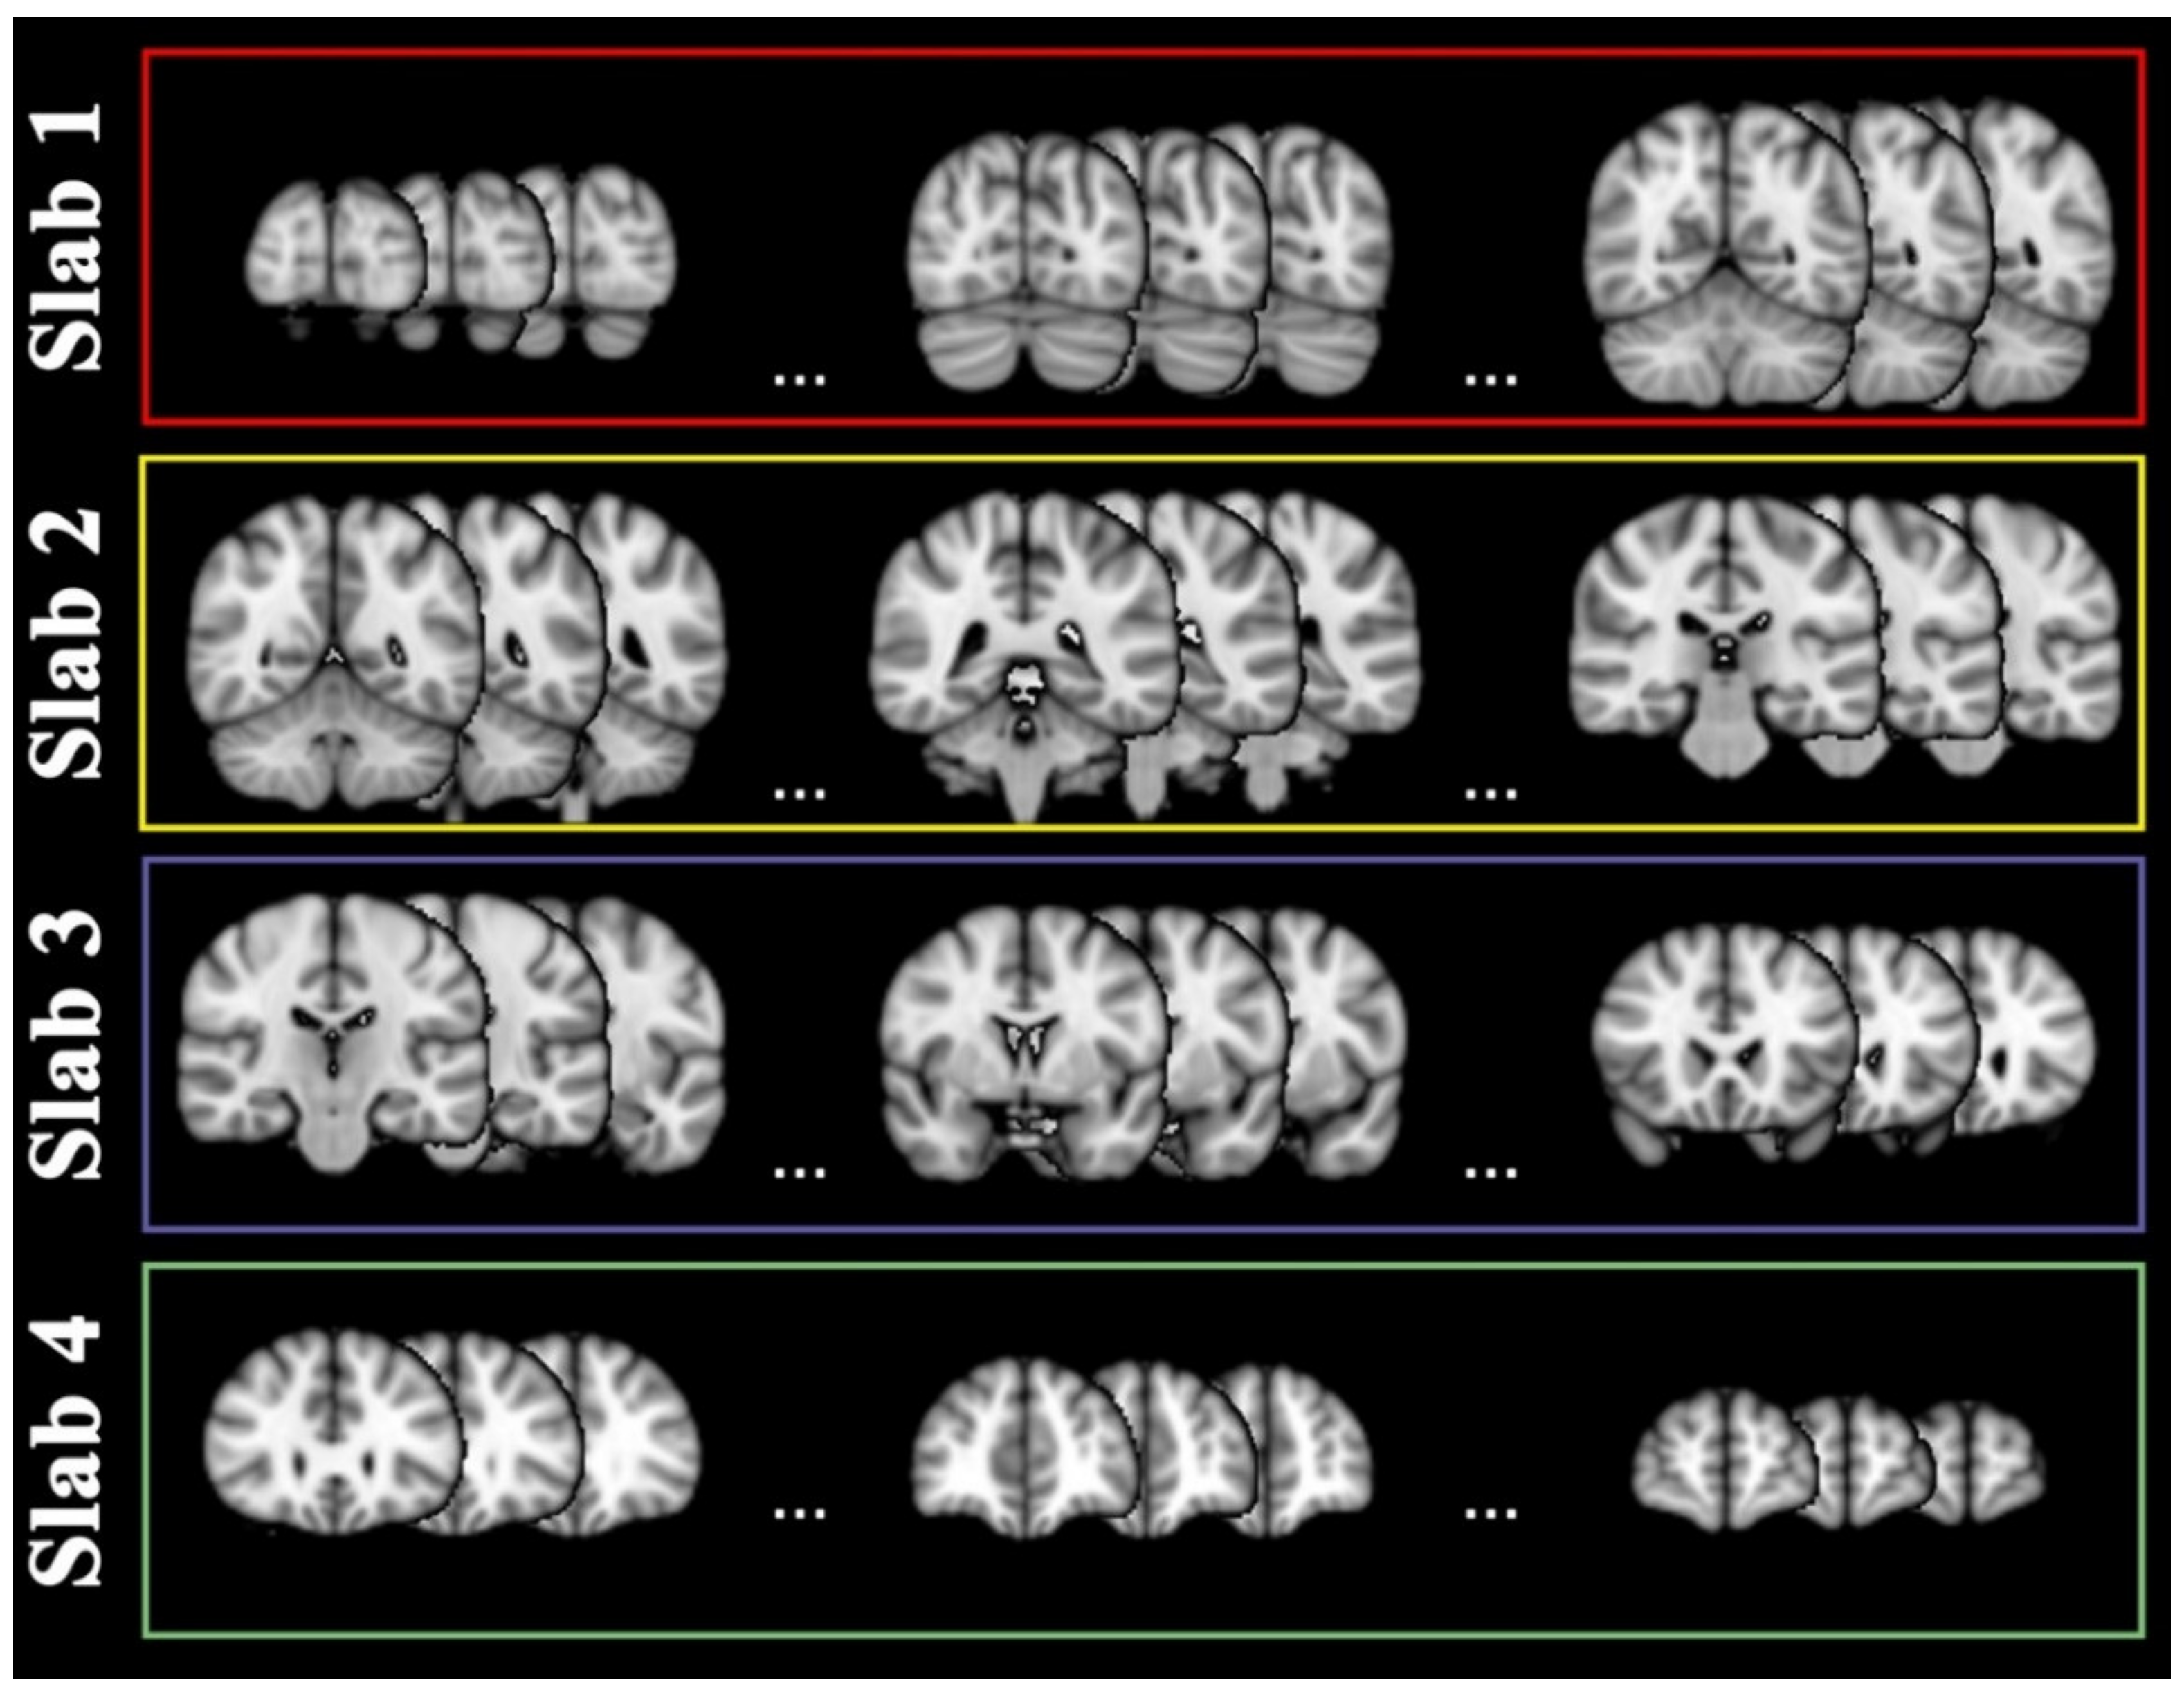

4.4. Slab Selection